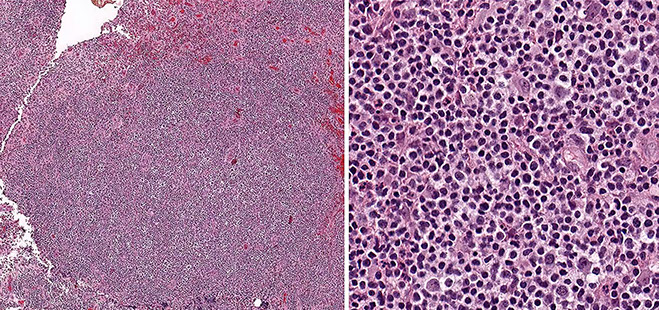

Anaplastic large cell lymphoma (ALCL), ALK positive

Anaplastic large cell lymphoma (ALCL), ALK negative